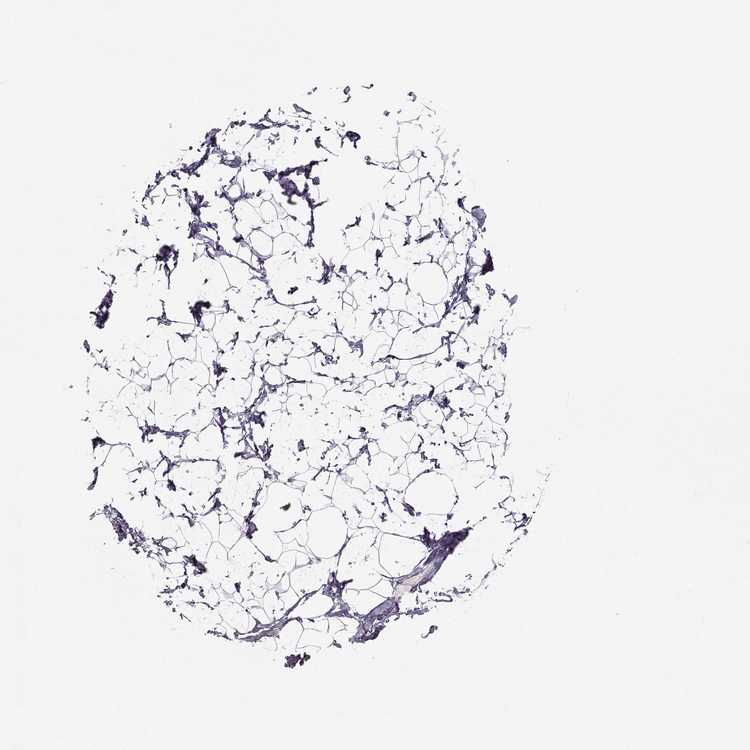

BREAST - Antibody stainingi

Antibody staining in the annotated cell types in the current human tissue is reported as not detected, low, medium, or high, based on conventional immunohistochemistry profiling in selected tissues. This score is based on the combination of the staining intensity and fraction of stained cells.

Each image is clickable and will lead to virtual microscopy that enables deeper exploration of all samples and also displays staining intensity scores, fraction scores and subcellular localization as well as patient and tissue information for each sample.

Antibody HPA055162

Adipocytes Not detected

Glandular cells Not detected

Myoepithelial cells Not detected